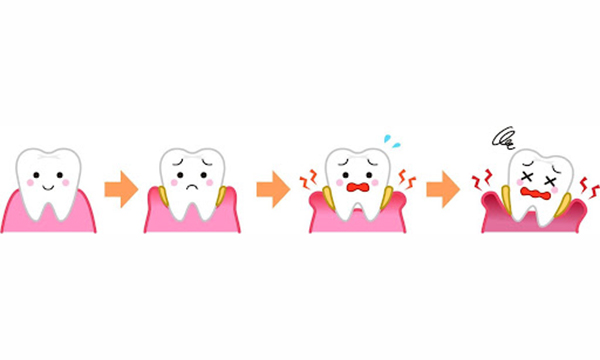

歯周病とは、細菌によって歯の周りにある組織(歯ぐきや歯を支える骨)がダメージを受ける病気です。「歯肉炎」や「歯槽膿漏」という言葉がありますが、それらを一つにまとめて表現した言葉が歯周病です。

歯周病の症状レベル

重度歯周病

特徴

歯周炎の段階です。

- 歯がグラつく、抜け落ちそう

- 歯ぐきからの出血が長期間、またはずっと続く

- 歯ぐきから膿がでる

- 口臭が強い

- 歯ぐきが下がって歯と歯の隙間が目立つ